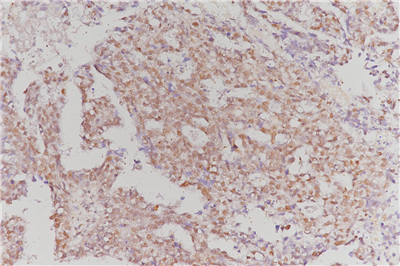

免疫组化是应用免疫学基本原理——抗原抗体反应,即抗原与抗体特异性结合的原理,通过化学反应使标记抗体的显色剂(荧光素、酶、金属离子、同位素) 显色来确定组织细胞内抗原(多肽和蛋白质),对其进行定位、定性及定量的研究,称为免疫组织化学技术(immunohistochemistry)或免疫细胞化学技术(immunocytochemistry)。

免疫组化的分类: 免疫组织化学技术按照标记物的种类可分为免疫荧光法、免疫酶法、免疫铁蛋白法、免疫金法等。

服务内容:包含抗体,包埋,切片,染色以及拍照。(每个样本提供一张照片包含阳性面积)加拍另外计费。